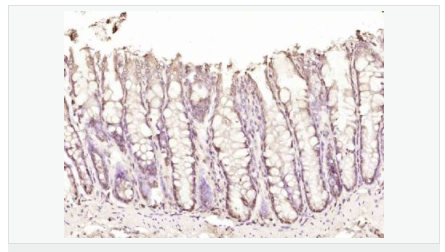

產品介紹his gene encodes a basic, proline-rich, 15-kD protein. The protein acts as a positive mediator of programmed cell death that is induced by interferon-gamma.

Function:

Negative regulator of autophagy. Involved in mediating interferon-gamma-induced cell death.

Post-translational modifications:

Phosphorylated. Phosphorylation by MTOR inhibits the suppressive activity of DAP toward autophagy.